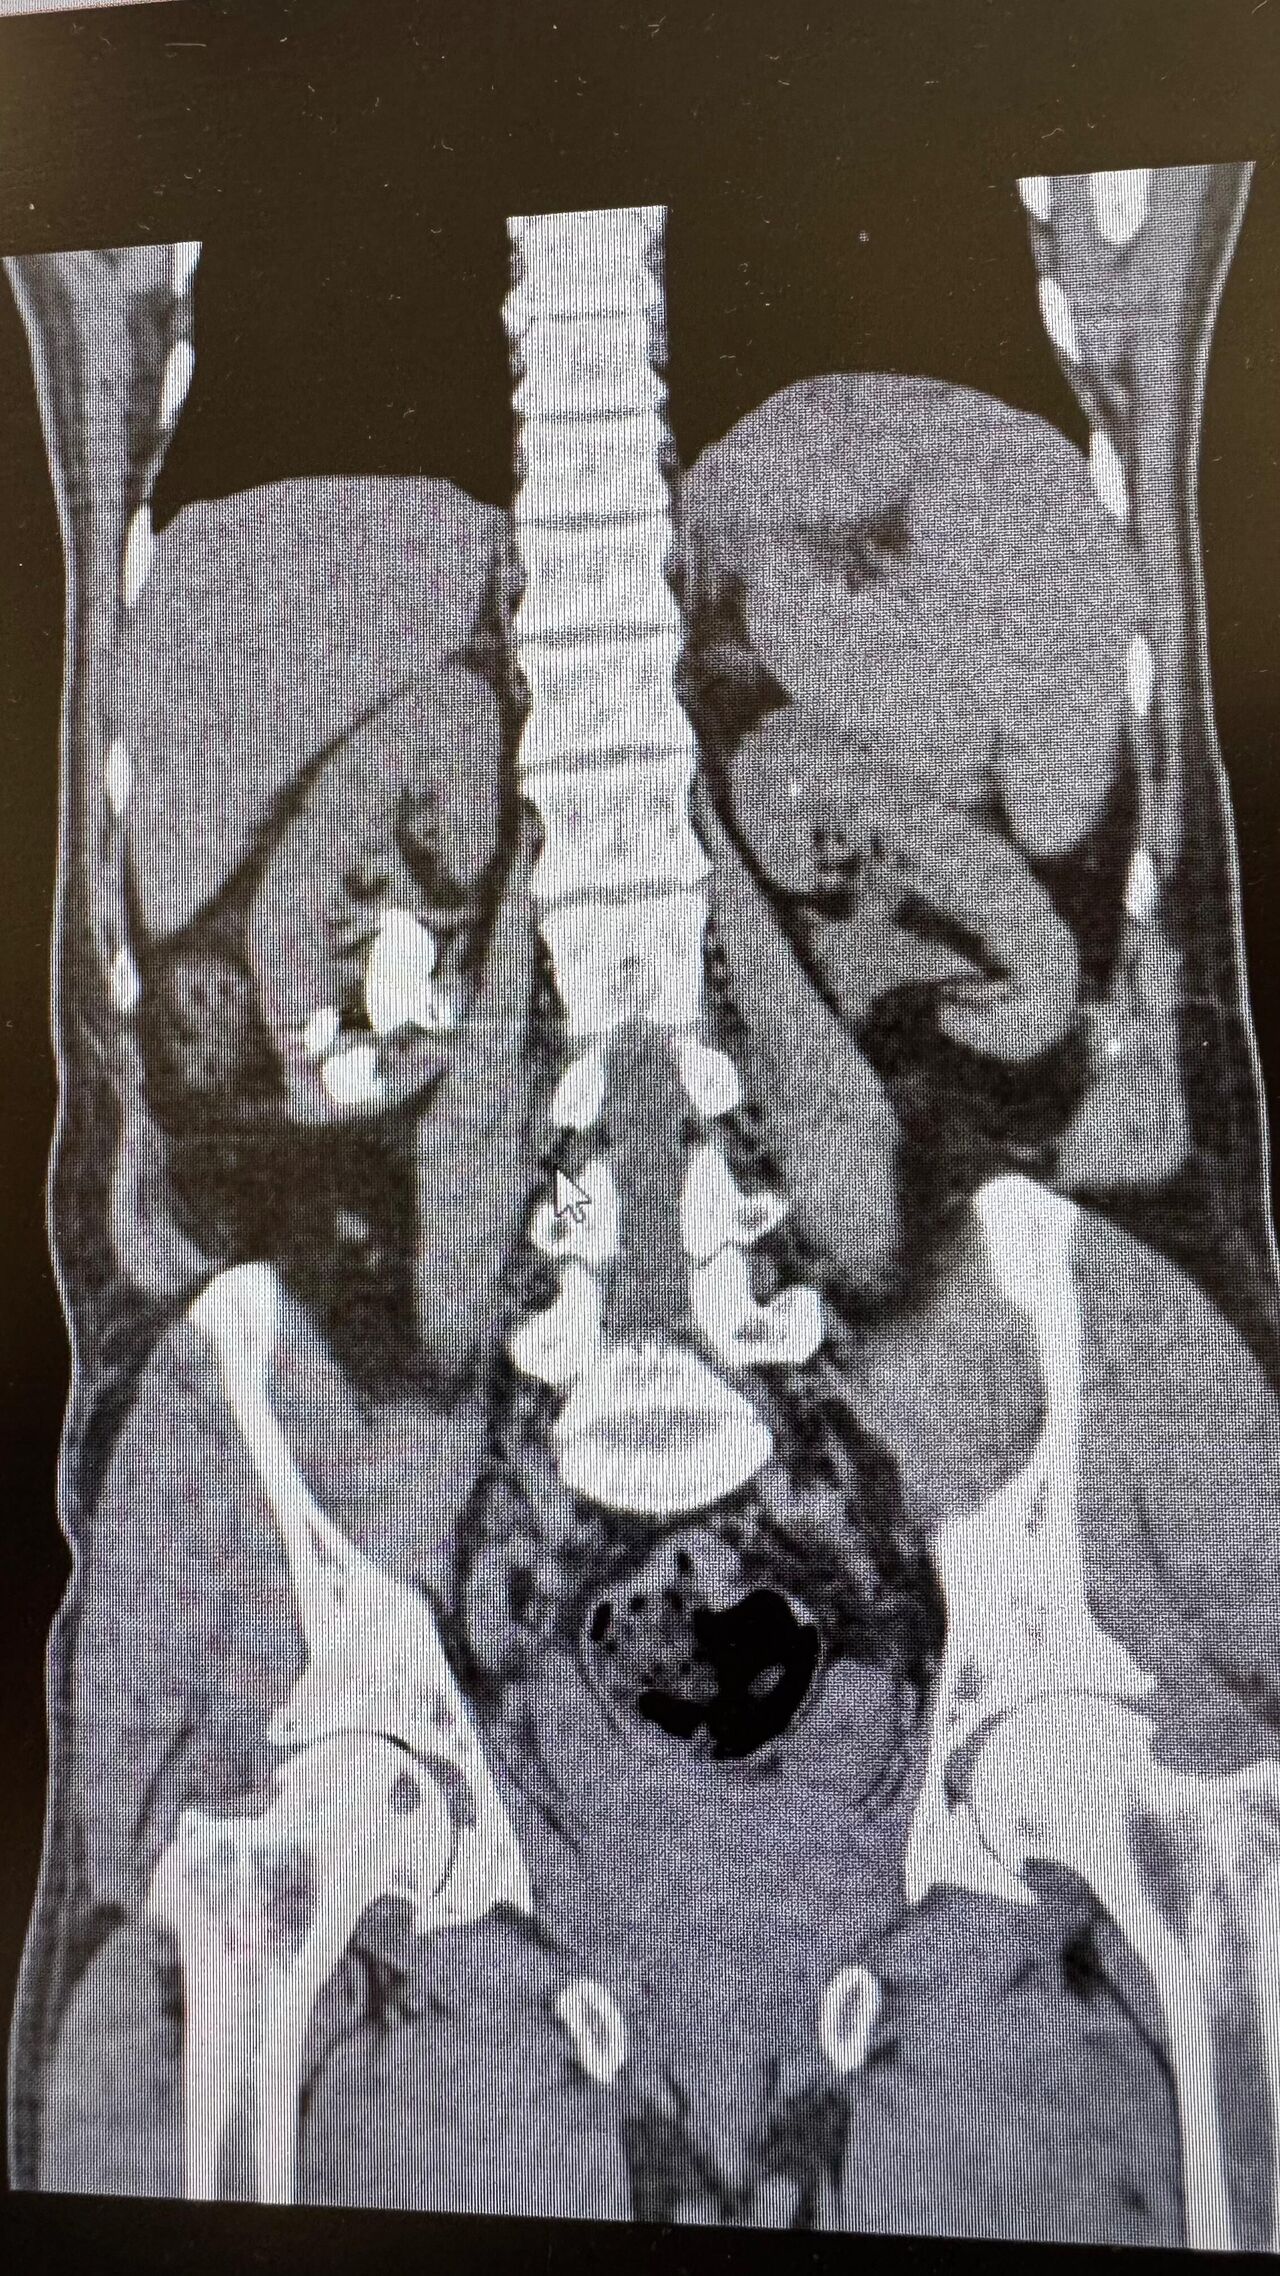

Üroloji Uzmanı Op. Dr. İlker Fatih Şahiner ve ekibince kapalı yöntemle (PNL) yapılan ameliyatlarda hastanın her iki böbreğindeki tekrarlayan sistin taşları temizlendi. Hastanın daha önce 10'un üzerinde böbrek taşı ameliyatı geçirdiği öğrenildi. Mayıs ayında yapılan ilk operasyonla sol böbrekteki taşlar alınırken, geçtiğimiz salı günü gerçekleştirilen ikinci operasyonla sağ böbrekteki taşlar da temizlendi.

Operasyonları gerçekleştiren Üroloji Uzmanı Op. Dr. İlker Fatih Şahiner, "Hastamızın her iki böbreğinde de tekrarlayan sistin taşları mevcuttu. Mayıs ayında sol böbreğine PNL yaparak taşsızlık sağlamıştık. Dün de sağ böbreğine PNL ameliyatını yaparak taşsızlık sağladık. Hastamızın genel durumu iyi, tedavisi servisimizde devam ediyor" dedi.